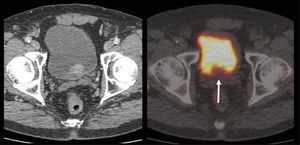

El PET/CT utilizando F18-FDG, dado la excreción fisiológica por vías urinarias del radiotrazador, no es propicio para la evaluación de los tumores primarios (16). Cuando los tumores muestran similar captación de F18-FDG que el contenido urinario, pueden no ser visibles salvo en las imágenes de TC (15). En cambio, si el tumor es más captante que la orina (Figura 3), o menos (Figura 4), puede ser detectado realizando un adecuado ventaneo de la imagen del PET.

El contraste fisiológico de las vías urinarias no es un problema respecto a la detección de compromiso ganglionar y a distancia, que representa el verdadero aporte del PET/CT en estos pacientes, al detectar pequeños ganglios que no constituyen adenopatías en el UroTAC (Figuras 4 y 5), y pesquisar siembra secundaria a distancia con mayor sensibilidad que las técnicas convencionales (17).